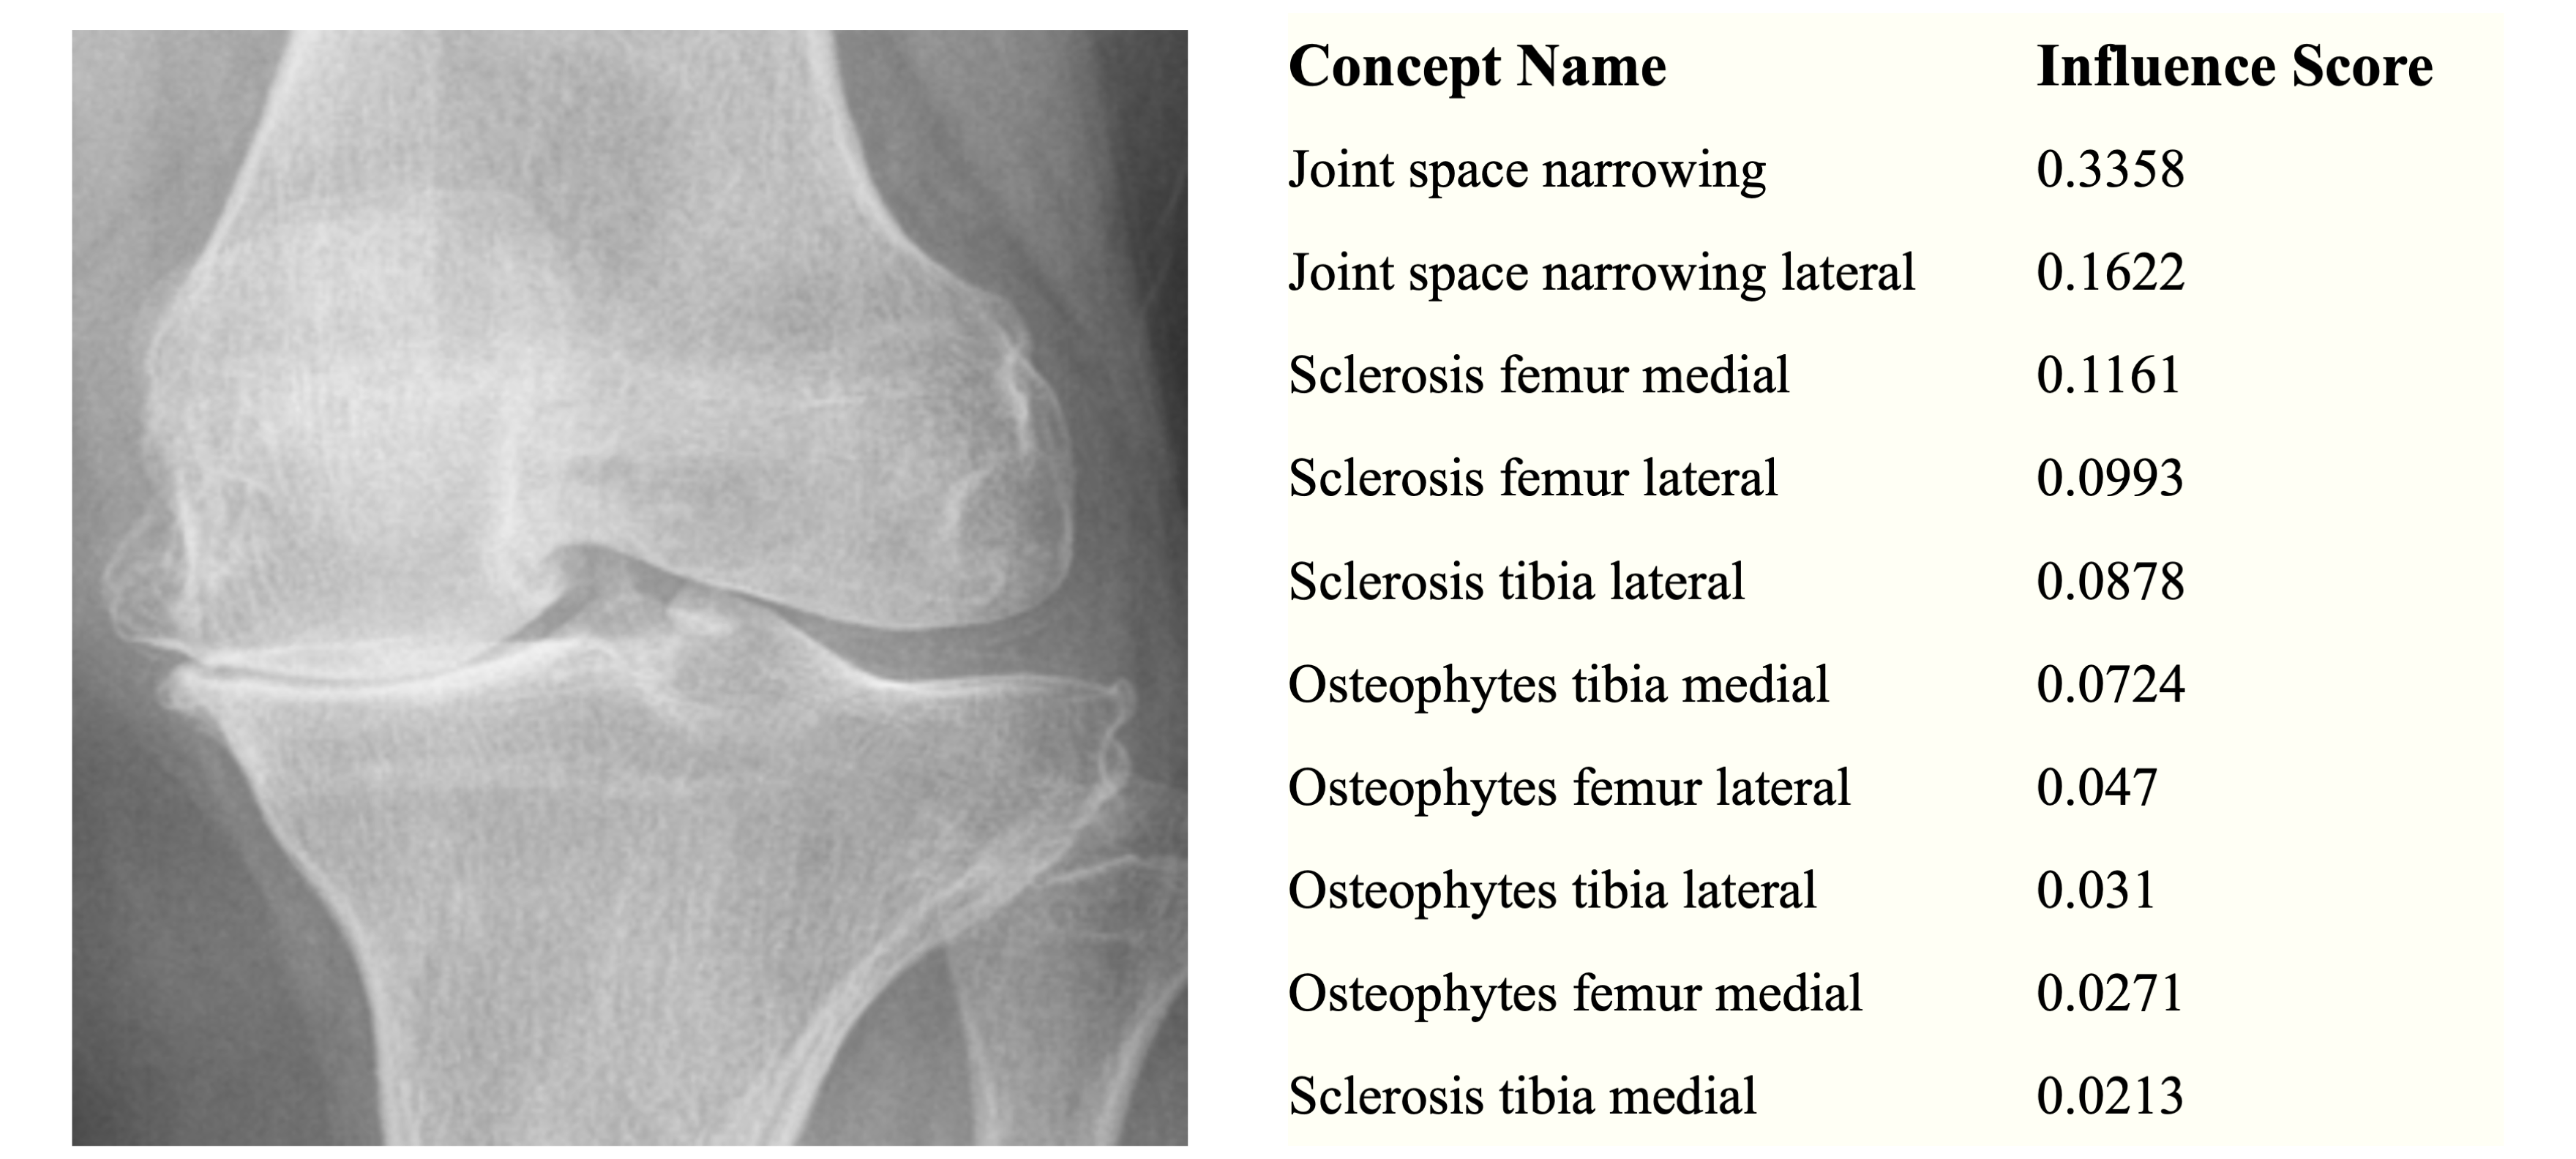

Datasets. We evaluate our method on four diverse benchmarks: X-ray Grading (OAI) [nevitt2006osteoarthritis], Bird Identification (CUB) [wah2011caltech], Large-scale CelebFaces Attributes (CelebA) [liu2015deep], and Derm7pt [combalia2019dermoscopy].

OAI: A multi-center observational study of knee osteoarthritis comprising 36,369 data points. We configure concepts characterizing crucial osteoarthritis indicators (e.g., joint space narrowing, osteophytes). Following the protocol in [koh2020concept], we preprocess the data to align with standard CBM setups.